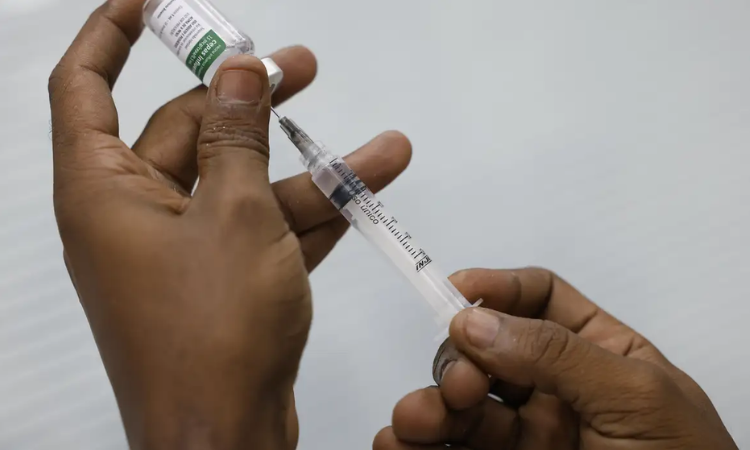

Imagem: Fernando Frazão

A mobilização nacional para conter o avanço da gripe ganha um reforço decisivo neste sábado (28/03/2026). O "Dia D" marca o início da Campanha Nacional de Vacinação contra a Influenza, que seguirá até o dia 30 de maio nas regiões Sul, Sudeste, Centro-Oeste e Nordeste. A estratégia antecipa o período de maior circulação do vírus nestas localidades, enquanto na região Norte a imunização ocorrerá no segundo semestre devido à sazonalidade específica da doença.

Para a campanha deste ano, o Ministério da Saúde já distribuiu 15,7 milhões de doses da vacina trivalente, que foi atualizada para combater as novas cepas do vírus em circulação no Brasil. A imunização é gratuita e está disponível em todas as Unidades Básicas de Saúde (UBS). A iniciativa é fundamental diante dos dados epidemiológicos de 2026, que já registram 14,3 mil casos de Síndrome Respiratória Aguda Grave (SRAG) e cerca de 840 óbitos até meados de março, sendo a influenza responsável por 28,1% das infecções graves identificadas.

Órgãos de vigilância epidemiológica e secretarias de saúde desempenham funções fundamentais no licenciamento de imunizantes, monitoramento de casos e fiscalização da rede de frio para armazenamento das doses. Esse trabalho de vigilância técnica é essencial para garantir a eficácia da vacina, assegurando que o controle de doenças respiratórias ocorra com rigor científico e segurança para toda a população brasileira, fortalecendo o Sistema Único de Saúde (SUS).